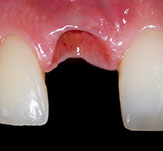

Fig. 12-13-14: Every demanding aesthetic treatment involving implants should have a provisional phase before the definitive prosthesis is delivered. It is mandatory to design natural emergence profiles before finishing the treatment.

7) Managing provisionals in implants in the aesthetic zone. Current concepts.

During the provisional phase of the treatment, a correct and natural emergence profile should be created following the adjacent tooth.